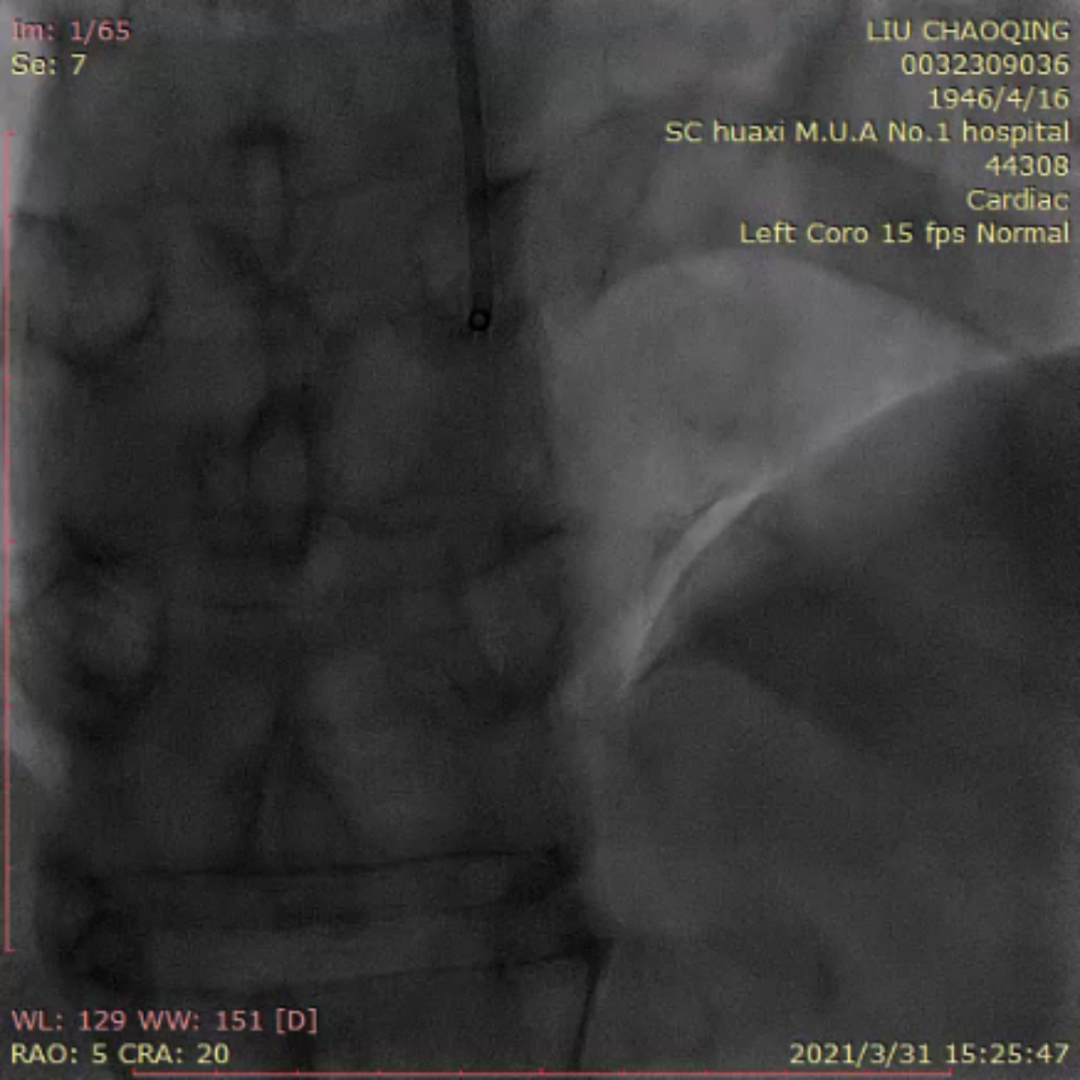

来自四川大学华西医院的李晨教授为大家分享了一例ADR开通前降支CTO的疑难病例。患者为老年男性,反复活动后胸痛6月。当地医院冠脉造影提示前降支完全闭塞,尝试PCI未能成功开通血管。予规范药物治疗,患者仍反复有胸痛入院。患者两段CTO,闭塞段长,钙化重,成角,前次失败,J-CTO 4分,右窦上方侧枝供应间隔-前降支;回旋支自身侧枝供应对角支;右冠无明显侧枝;前降支中段着陆区条件较好,ADR着陆区条件尚可。

前降支开口完全闭塞,似见残端

前降支近段可见岛状显影伴钙化

岛状显影处似与对角支相连;但造影剂消散慢,不排除假腔未愈合

前降支中远段可见自身逆向侧枝

右冠远端重度狭窄

右冠窦上方侧枝供应前降支

右窦造影显示侧枝较扭曲

双侧造影:右冠侧枝条件差,自身侧枝供应对角支